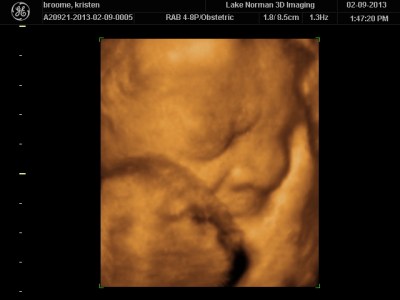

..We meet again, little boy!